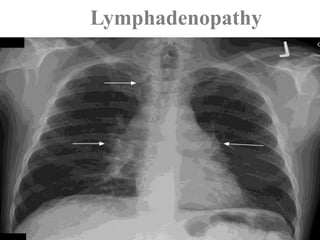

LYMPH NODESsarcoidosis

Sarcoidosis of Lymph nodes

Lymph nodes are involved in almost all cases

particularly the hilar and medistinal nodes.

Any other nodes may be involved.

Nodes are characteristically enlarged discrete and

sometimes calcified.

Lymphadenopathy

Typical

Bilateral hilar & right paratracheal LN.

Middle mediastinal LN occur in 50% of cases.

Left paratracheal, aorto-pulmonary & subcarinal LN.

1-2-3 sign present in 95% of cases. This is called

Garland triad

Enlarged bilateral hilar, right paratracheal (arrow), and

aortopulmonary window (arrowhead) nodes.